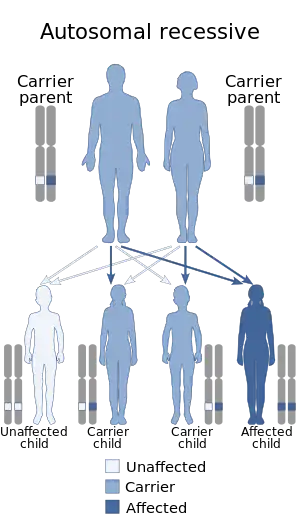

Krabbe disease (KD), also known as globoid cell leukodystrophy[3] and galactosylceramide lipidosis[4], is a rare and often fatal lysosomal storage disease that results in progressive damage to the nervous system. KD involves dysfunctional metabolism of sphingolipids and is inherited in an autosomal recessive pattern. The disease is named after the Danish neurologist Knud Krabbe (1885–1961).[5]

Krabbe disease is caused by mutations in the GALC gene located on chromosome 14 (14q31),[8] which is inherited in an autosomal recessive manner. Mutations in the GALC gene cause a deficiency of an enzyme called galactosylceramidase.[9] In rare cases, it may be caused by a lack of active saposin A (a derivative of prosaposin).[1]